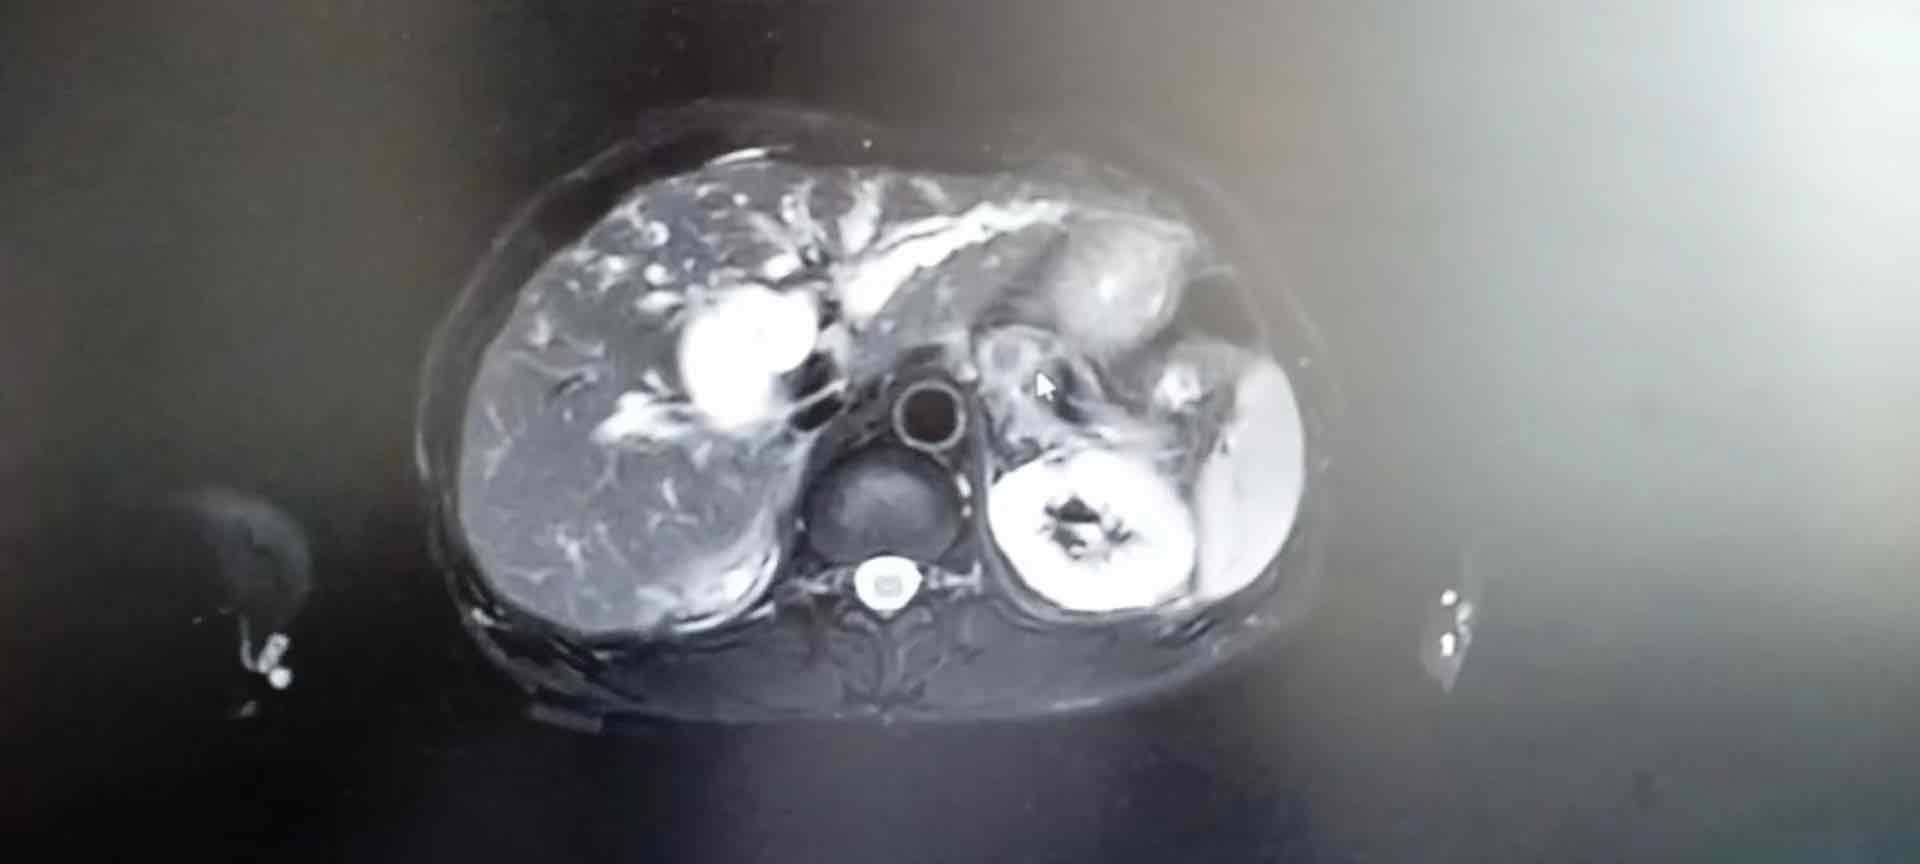

2022年10月23日叫二姐带父亲去人民医院复查卡肺的恢复情况,照了MRI,提示显示十二指肠占位,这消息简直是炸弹,我都快被整疯了,我当时有点不太相信报告结果,另外人民医院的医生水平我一直不太放心,所以这次检查的结果我没有放在心上,我在想下次去武汉同济复查看下到底什么情况